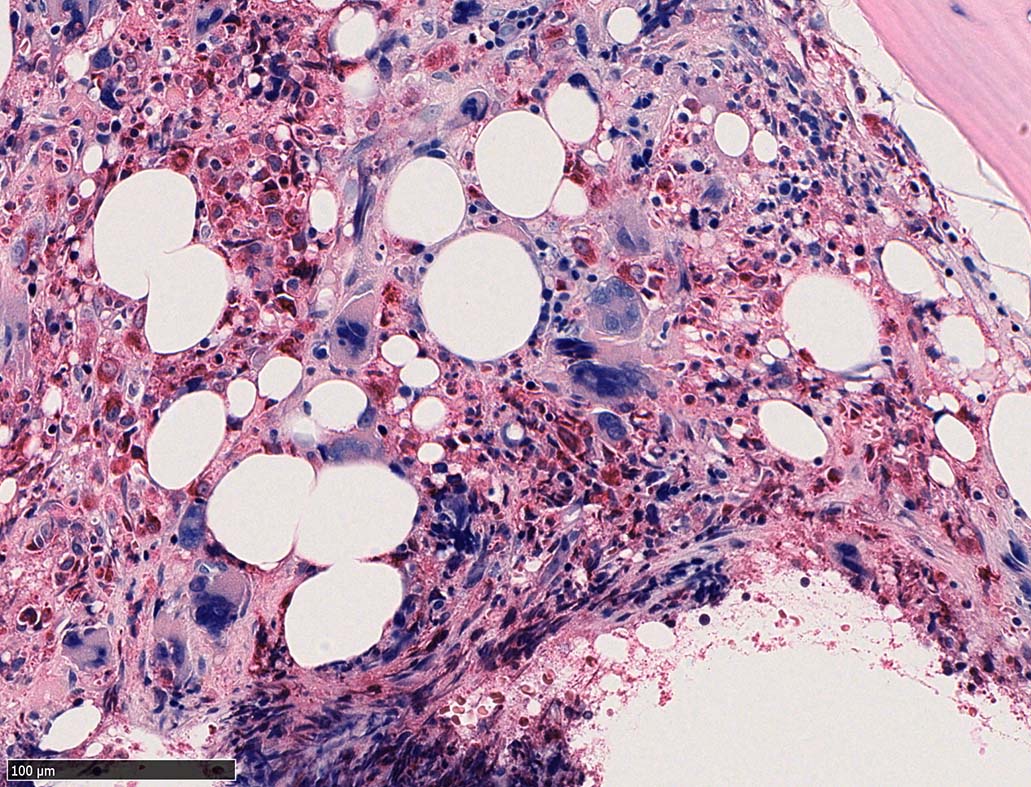

Case02; Meylofibrosis, overt fibrosis

77year-old female. 40歳時polycythemia veraと診断されていた.

[注] この症例は詳細は不明であるが, 過去にPVと診断されているため, PVに伴う二次性のmyelofibrosisの診断になる.

黒染する弾性線維の増生のほか, 赤く染まる膠原線維の増生が確認される. MF-2 fibrosis. 鍍銀染色の核染色をすると膠原線維の赤染がわからなくなるので行わない.